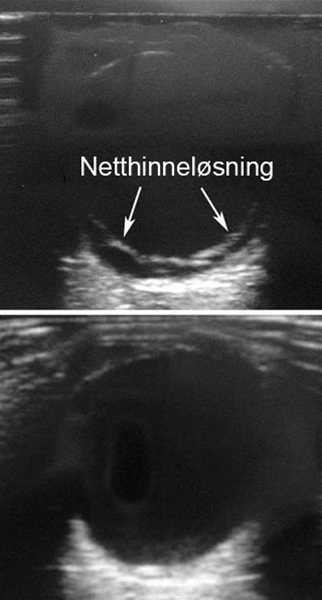

I det øverste billede peger pilene på en afløst nethinde. Det nederste billede viser et ultralydsbillede af et normalt øje, hvor nethinden ikke er afløst.